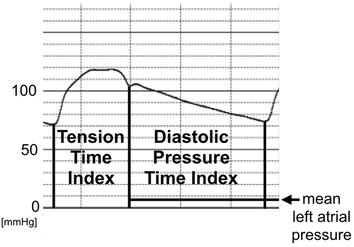

Subendocardial Viability Ratio

The subendocardium is thought to be more sensitive to a shortage of blood supply than the subepicardium. Buckberg and colleagues demonstrated that the ratio of the diastolic phase area (diastolic pressure time index) to the area of the systolic phase (tension time index) in the central aortic pressure profile has a close correlation to the blood supply to the subendocardium [5,6,7]. The ratio was designated as the subendocardial viability ratio:

Therefore, they coined this index as a measure of the hemodynamic capacity for the supply divided by the myocardial oxygen demand. The tension time index was obtained by measuring the area under the aortic systolic pressure curve and it equaled the mean aortic systolic pressure multiplied by the duration of systole. The diastolic pressure time index was obtained by measuring the area under the diastolic aortic pressure curve and subtracting the mean left atrial pressure (assumed to be equal to the left ventricular diastolic pressure) multiplied by the diastolic time from it. When the left atrial pressure was not recorded, we used the pulmonary capillary wedge pressure instead.